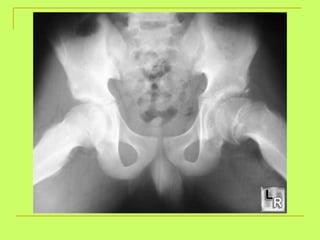

Age from hip bone examination: Two pubic rami of the hip  (6y) Suture at the acetabulum  (15y). Ischeal tuberosity with the ischium  (21y). Iliac crest with the ilium  (23y).

What is the age ? From4-6 Open ischial ramus(less than6) >4years (ossific center at greater trochanter) <15years (opened triradiate suture)

What is the age ? >4 y (ossific center at greater trochanter)<15 y  (triradiate suture is opened )

What is the age? <23 y (non-united iliac crest)

Age from hipbone examination: Two pubic rami of the hip (6y) Suture at the acetabulum (15y). Ischeal tuberosity with the ischium (21y). Iliac crest with the ilium (23y).

What is theage ? From4-6 Open ischial ramus(less than6) >4years (ossific center at greater trochanter) <15years (opened triradiate suture)

What is theage ? >4 y (ossific center at greater trochanter)<15 y (triradiate suture is opened )

What is theage? <23 y (non-united iliac crest)